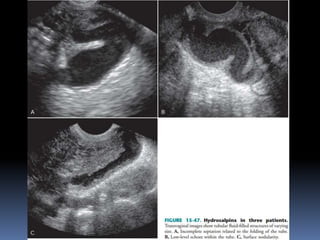

This document contains an image gallery from Dr. Mohit Goel showing various uterine anomalies and ovarian cysts. It includes images of an arcuate and unicornuate uterus, endometritis, a twisted ovarian pedicle, dermoid cysts of varying sizes and echogenicity containing hair, fat, and calcifications, and a combination dermoid cyst showing both mesh and plug structures. The gallery provides ultrasound images of different gynecological conditions for medical education and reference.